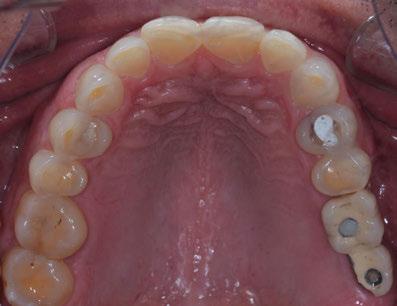

Se obtuvieron modelos de estudio (Figuras 3-6) digitales mediante un escáner confocal de luz azul estructurada (PrimeScan, Dentsply Sirona) y se planificó un protocolo de desgaste mínimamente necesario y conservador de las estructuras

dentarias, cumpliendo parámetros biológicos, terapéuticos, mecánicos y estéticos. Después se realizó un modelado digital retrospectivo (Figuras 7-11) para generar modelos impresos 3D para realizar el mock up funcional, estético y como guía para las preparaciones (Figuras 12-15). Con ello, se efectuaron las preparaciones dentarias y los registros intermaxilares y, posteriormente, se digitalizaron ambos maxilares (Figuras 16-21)

SW 5.2, Dentsply Sirona) (Figuras 22-27), la cual fue materializada en dos tipos de materiales a partir de bloques cerámicos IPS Empress CAD y cerámica vítrea de disilicato de litio IPS E.max CAD (Figuras 28-30)

Finalmente, las restauraciones se cementaron adhesivamente (Figuras 31-35). En las piezas 16 y 17 se realizaron restauraciones cementoatornilladas como última fase de tratamiento. Se recomendó al paciente una férula de protección superior la cual fue elaborada mediante un flujo de trabajo digital (Figura 36)